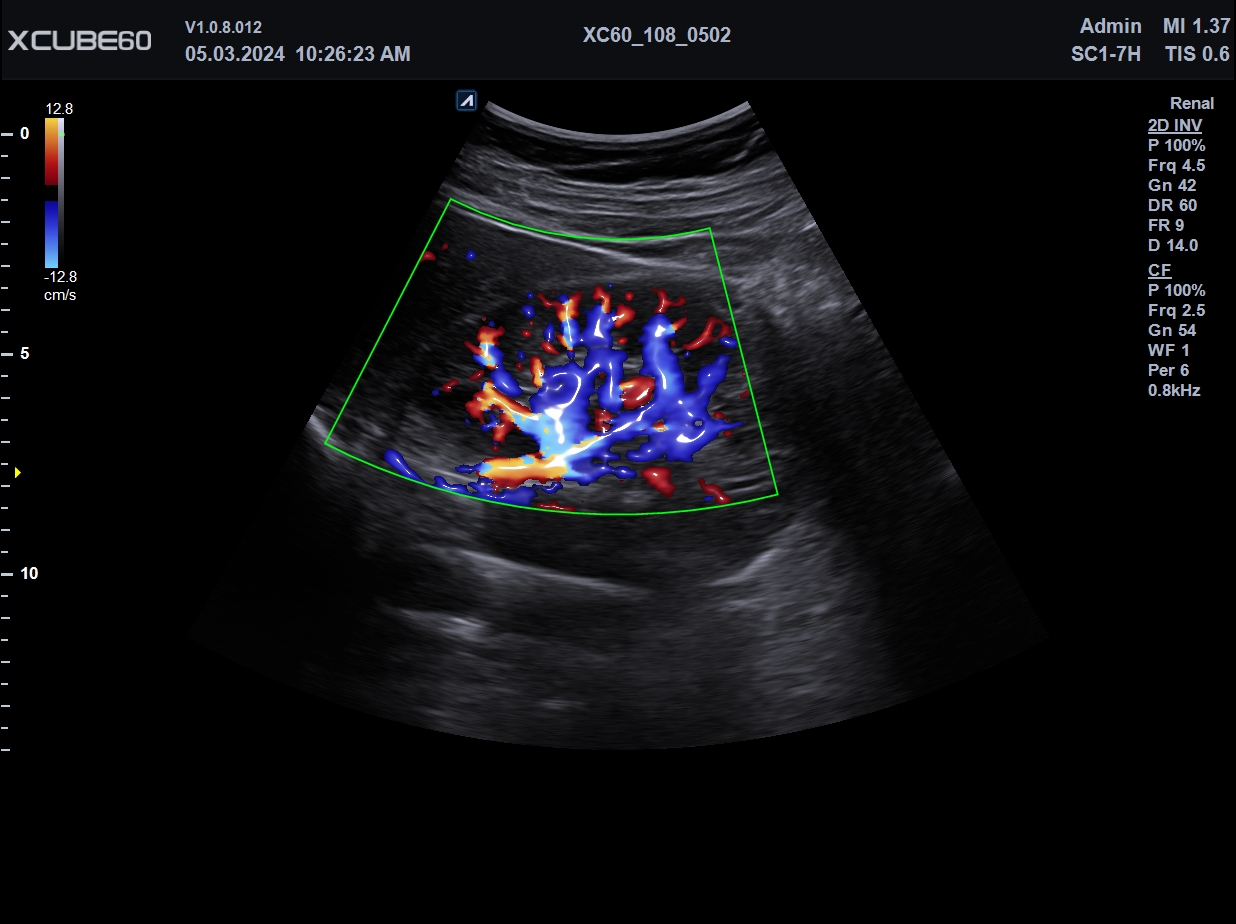

El X-CUBE 60 se desarrolló para brindar un entorno de trabajo cómodo a la usuaria. El rendimiento óptimo de imagen se logra gracias a la arquitectura X+, el motor de imágenes de alta resolución de la serie X-CUBE, para un diagnóstico fiable de diversas enfermedades. Repetir el diagnóstico a diario agota al personal médico. Diversas funciones de medición automática, que se adaptan al flujo de trabajo del usuario, reducen el tiempo de diagnóstico, y la pantalla táctil de mayor tamaño y el panel de control intuitivo reducen la fatiga. Además, su tamaño compacto y versátil permite un uso eficiente del espacio en la sala de escaneo.

| Arquitectura del Sistema: | Arquitectura X+, Power View, FleXcan, SensitiView, X+ Cristal Signature, X+ Fit, Optimal Imaging Suite |